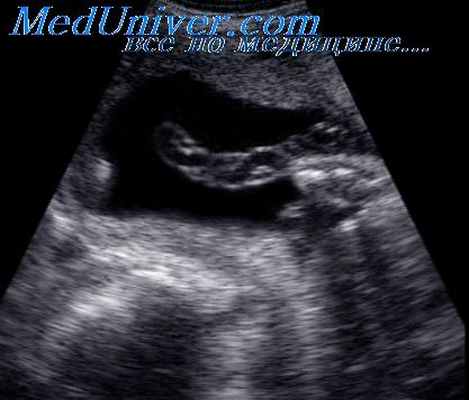

Гематомы пуповины могут иметь ятрогенное происхождение, если плоду выполняли кордоцентез. Такого рода гематомы всегда сочетаются с высокими перинатальными потерями. Так, по данным A.L. Dippel, в этих случаях мертворождения отмечались в 47%. Одним из механизмов внутриутробной гибели плода может быть спадение просветов сосудов пуповины из-за увеличеня на них давления со стороны вартонова студня, который пропитывается изливающейся кровью. Впервые диагноз гематомы пуповины был пренатально установлен и описан E.D. Ruvinsky et al. у пациентки с внутриутробной гибелью плода в 32 нед беременности.

При ультразвуковом исследовании в этот момент визуализировалось анэхогенное образование размером 6 х 8 см с перегородками, которое прилежало к передней брюшной стенке плода.